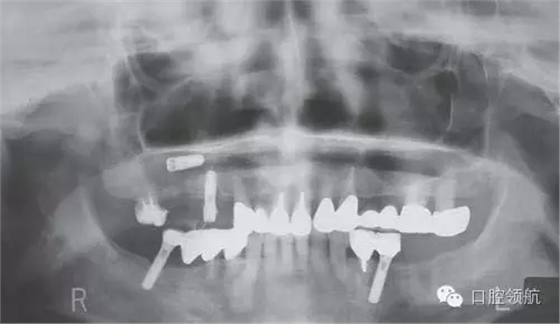

在外院進行上頜竇提升術(shù)7~8個月后,二次手術(shù)時發(fā)現(xiàn)種植體松動,在去除種植體時發(fā)生種植體進入上頜竇的情況。被介紹來我院就診,于當日進行了進入竇種植體的去除術(shù)(圖1、圖2)。

圖1 來院時的曲面斷層影像。